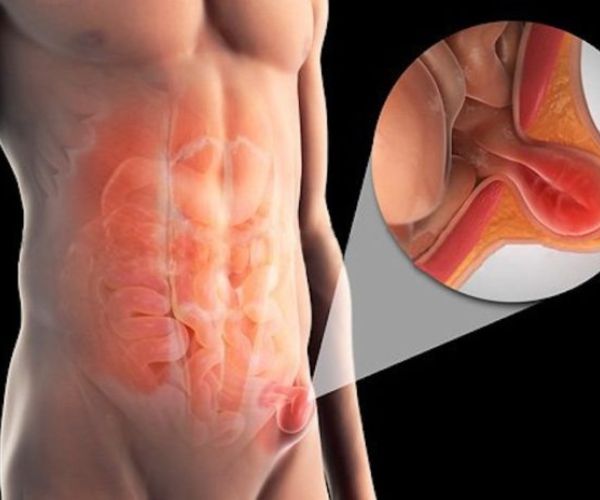

ما هو الفتق الإربي؟

الفتق الإربي من المشكلات الصحية الشائعة التي تصيب منطقة أسفل البطن، ويحدث عندما يضعف جزء من عضلات جدار البطن، مما يسمح لبعض الأنسجة أو الأعضاء الداخلية، مثل الأمعاء، بالاندفاع والبروز إلى الخارج من خلال هذه الفتحة الضعيفة.

- غالبًا يظهر الفتق الإربي على شكل انتفاخ أو بروز ملحوظ في منطقة أسفل البطن أو أعلى الفخذ، ويزداد وضوحه أثناء الوقوف، السعال، أو عند بذل مجهود بدني، وقد يصاحبه شعور بالألم أو عدم الراحة، خاصة عند الحركة أو رفع الأوزان.

- تختلف طرق التعامل مع الفتق الإربي حسب درجة شدته، ففي بعض الحالات البسيطة قد يُكتفى بالمراقبة واتباع إجراءات وقائية، بينما تتطلب الحالات المتقدمة أو المزعجة تدخلًا جراحيًا لإصلاح الضعف في جدار البطن ومنع المضاعفات.